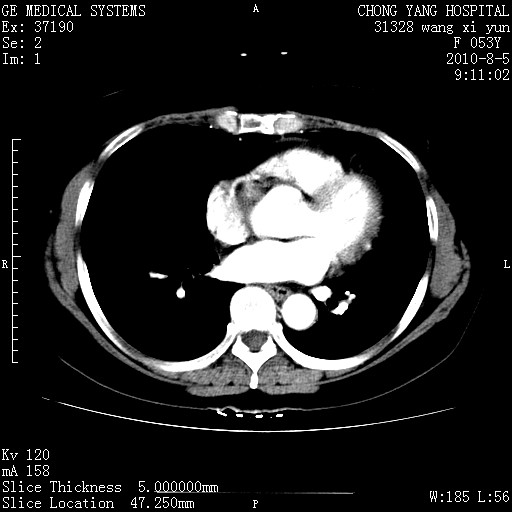

标题: CT28214:F41Y 血尿二十天,建议盆腔平扫加增强。

1)考虑肝左叶胆管细胞癌。2)脂肪肝。